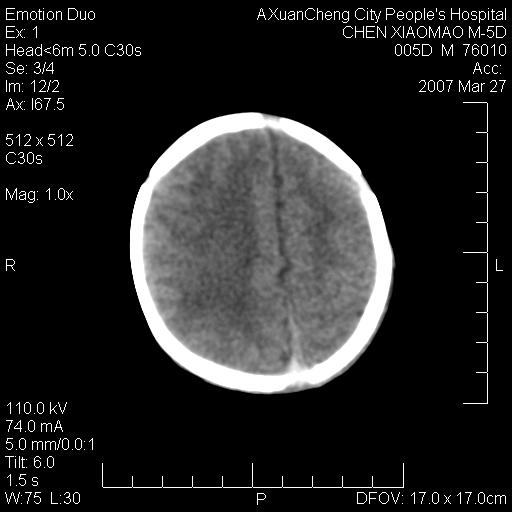

缝是正常的,但患儿有hie

大家看看可有hie ?还有左侧枕部胡形高密度ct为45~53hu,可有硬膜下血肿?

颅内未见明显异常。

颅内未见明显异常